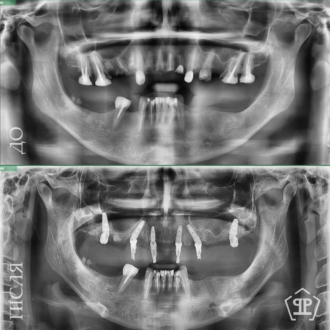

- виконання рентгенограми та КТ запланованого місця імплантації для визначення щільності щелепної кістки, ступеня її атрофії, наявності можливих патологічних вогнищ